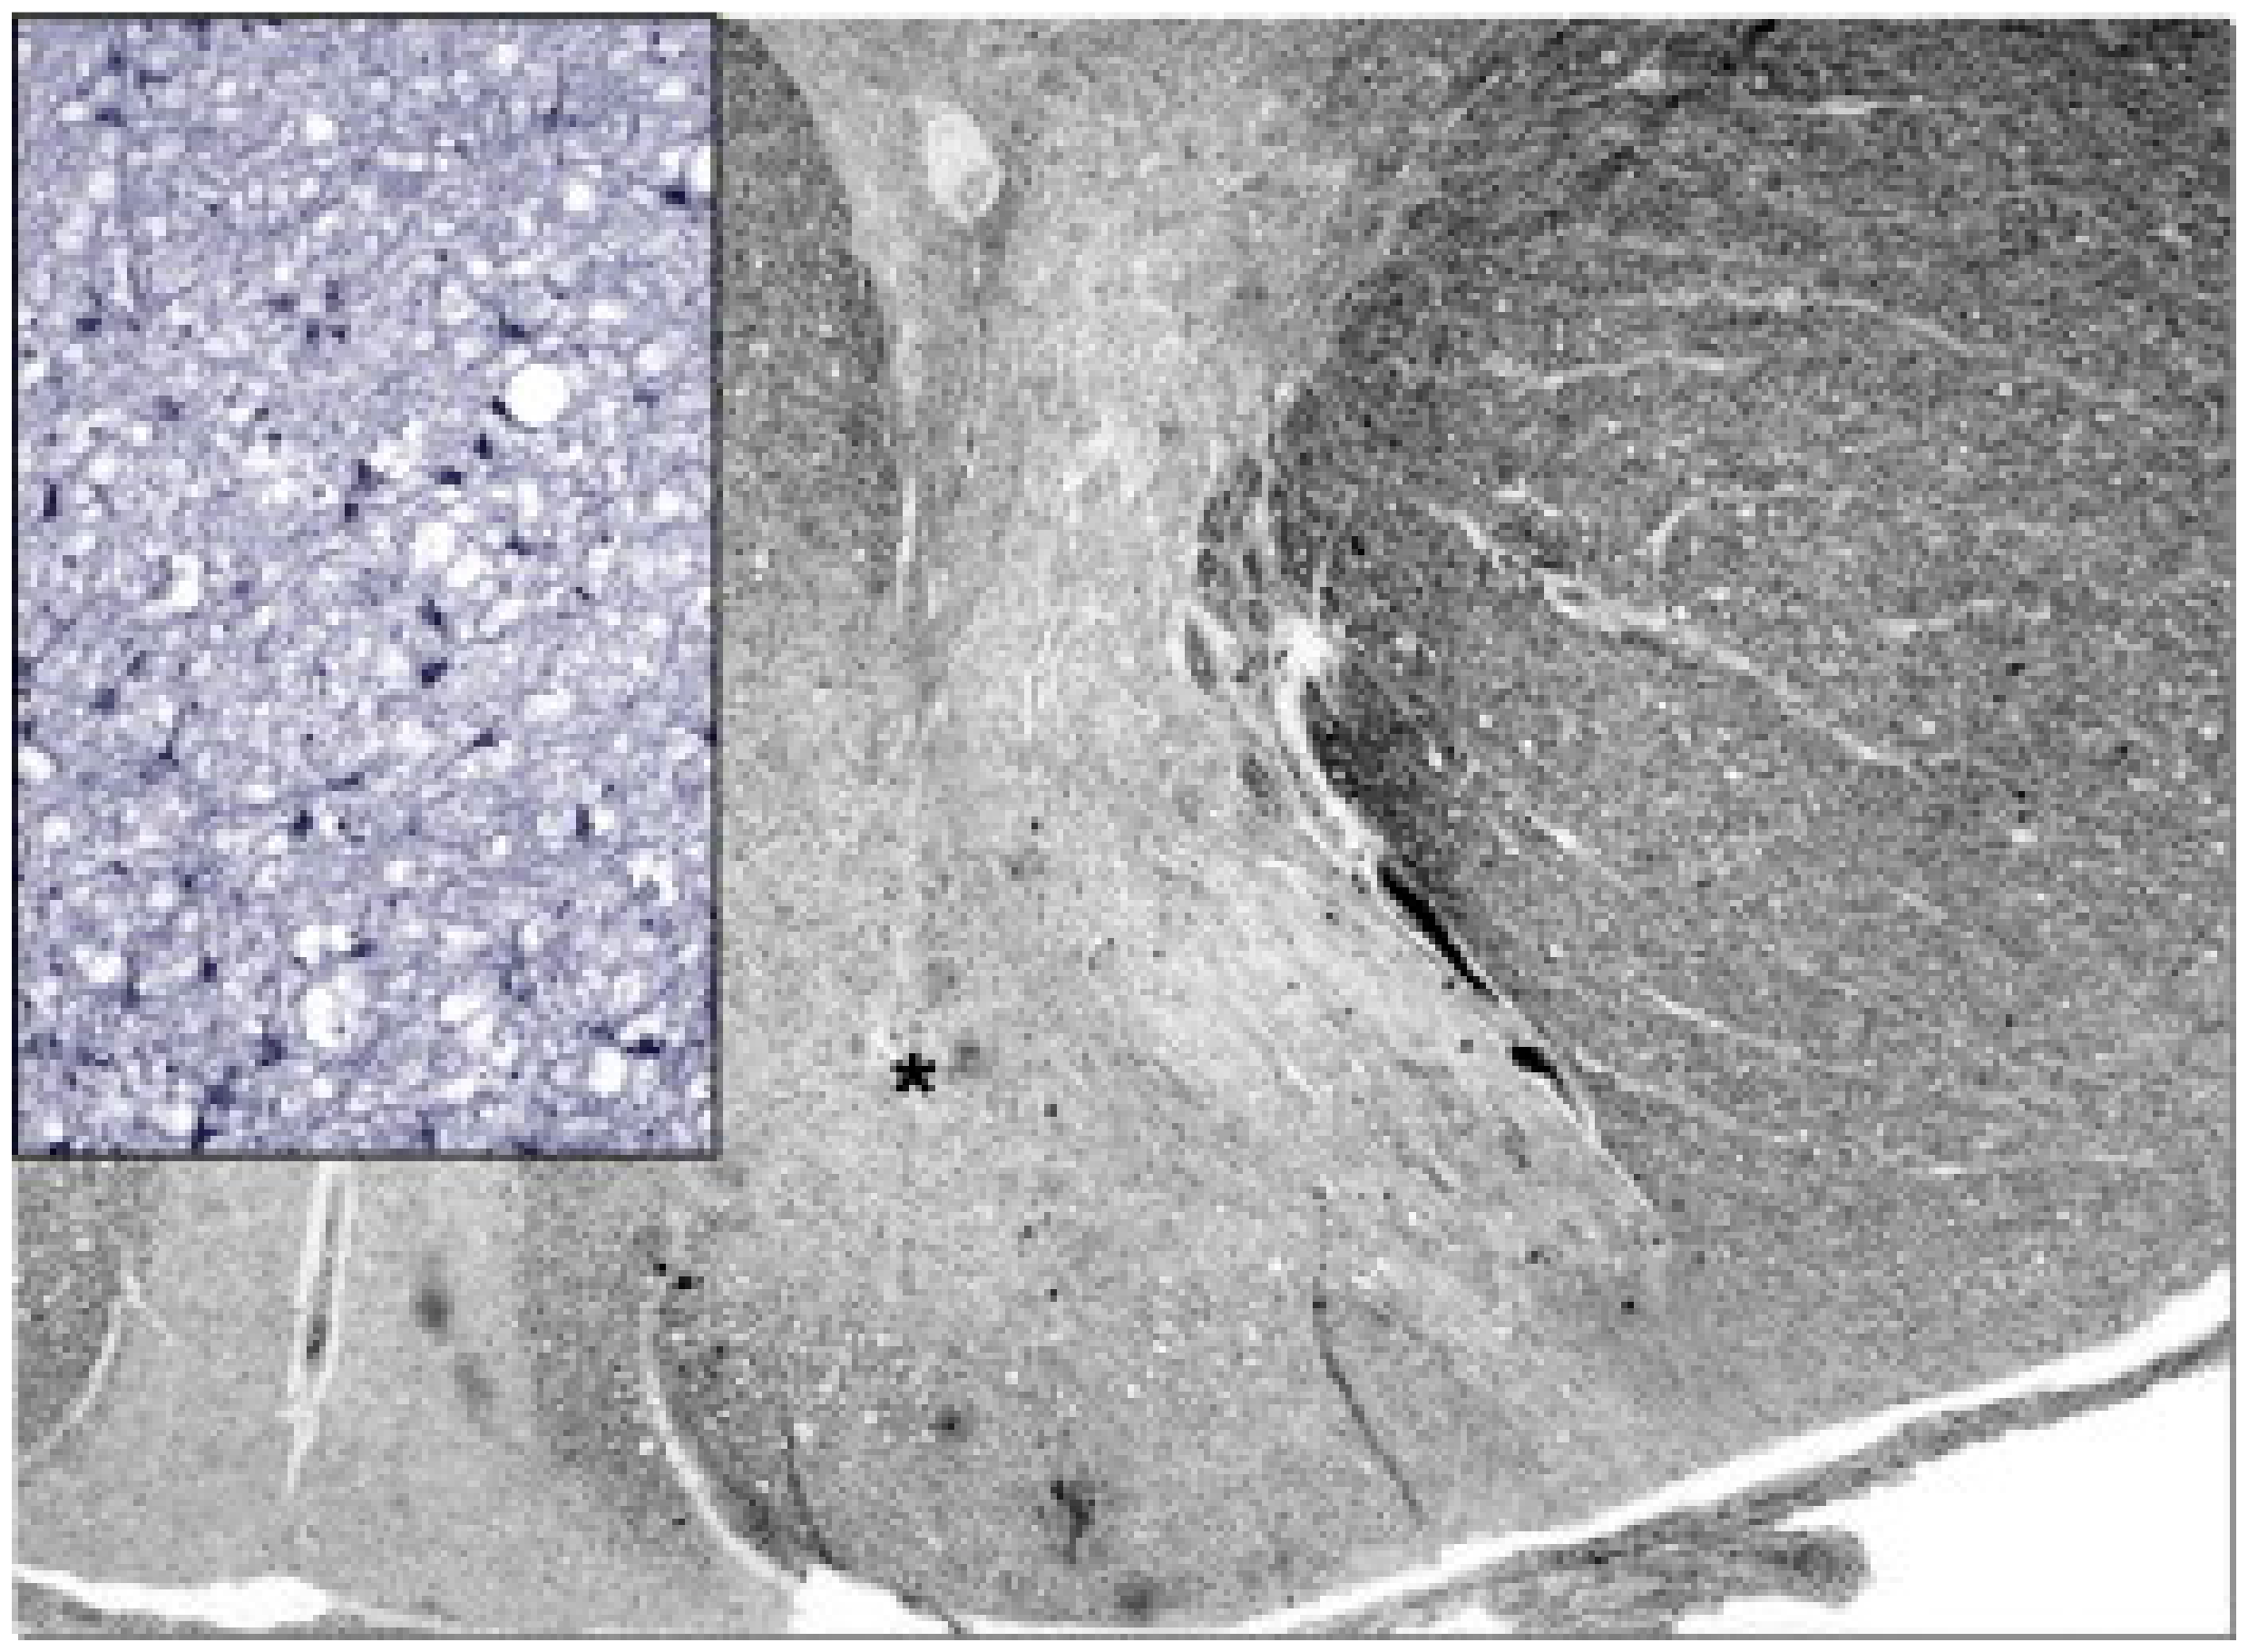

- Mizukami, K.; Sasaki, M.; Suzuki, T.; Shiraishi, H.; Koizumi, J.; Ohkoshi, N.; Ogata, T.; Mori, N.; Ban, S.; Kosaka, K. Central Nervous System Changes in Mitochondrial Encephalomyopathy: Light and Electron Microscopic Study. Acta Neuropathol. 1992, 83, 449–452. [Google Scholar] [CrossRef]

- Tsuchiya, K.; Miyazaki, H.; Akabane, H.; Yamamoto, M.; Kondo, H.; Mizusawa, H.; Ikeda, K. MELAS with Prominent White Matter Gliosis and Atrophy of the Cerebellar Granular Layer: A Clinical, Genetic, and Pathological Study. Acta Neuropathol. 1999, 97, 520–524. [Google Scholar] [CrossRef]

- Savoiardo, M.; Bruzzone, M.G.; D’Incerti, L.; Farina, L.; Grisoli, M. Metabolic and Genetic Diseases of the Brain. Riv. Neuroradiol. 1999, 12, 73–86. [Google Scholar] [CrossRef]